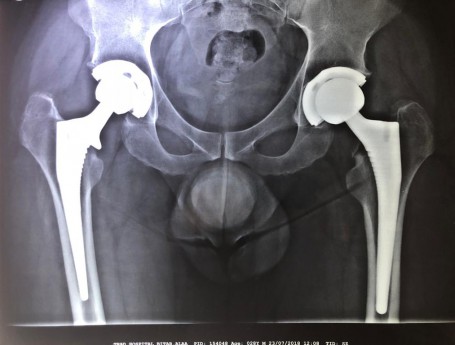

Bilateral Total Hip Arthroplasty Anterior Approach

• Bilateral Total Hip Arthroplasty Anterior Approach